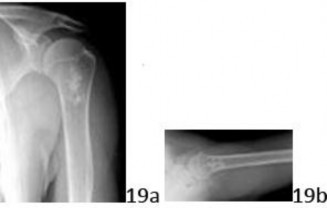

19a 19b A 15-year-old girl injured her shoulder in a fall while riding her bicycle. She reports a mild ache over the latter aspect of the shoulder, present since the accident, but denies any prior shoulder symptoms of any kind. AP and lateral radiographs shown in Figures 19a and 19b reveal a lesion in the proximal humerus. What is the most likely diagnosis?

DISCUSSION: This scenario represents the common "serendipitous" finding of benign chondroid lesions. The radiographs demonstrate the classic "rings and arcs" calcification of an enchondroma, in a commonly

presenting location (proximal humerus). The lesion is generally centrally located, and may have a well-defined lucent appearance, typically in the metaphysis of the bones. The other lesions listed do not have the typical calcification seen in these chondroid lesions. The mineral density in an osteoblastoma is more sclerotic and the lesion is often destructive. An aneurysmal bone cyst is purely lytic and generally expansile. Osteochondroma is an exophytic lesion, protruding outside the bone. Nonossifying fibroma is an eccentric, well-demarcated lesion with no mineral density. The Preferred Response to Question # 19 is 3.